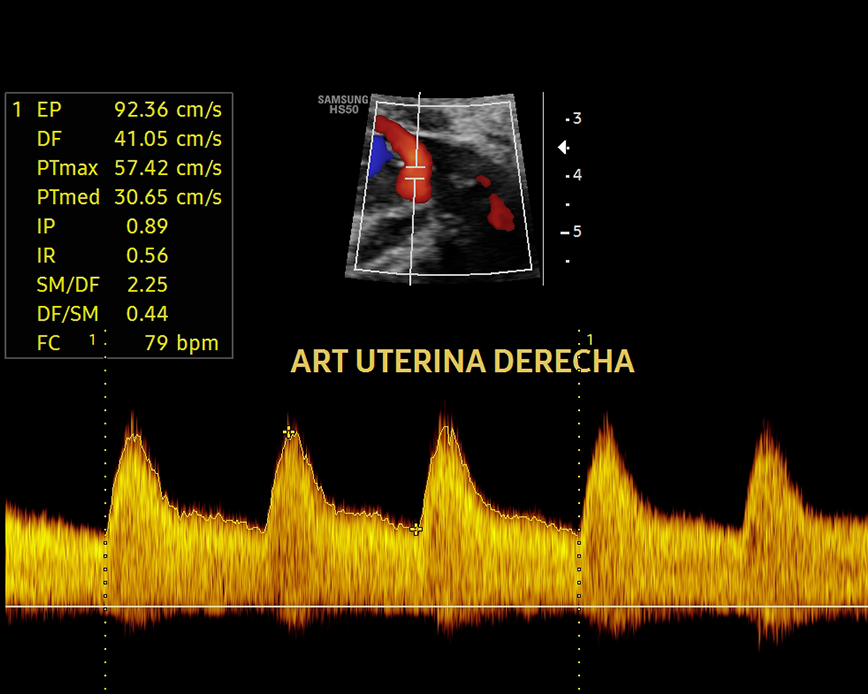

Esta ecografía sirve para evaluar la hemodinamia materno-fetal y detectar problemas de crecimiento como el RCIU (Restricción del Crecimiento Intrauterino) y el riesgo de preeclampsia (presión arterial alta durante el embarazo). Además, nos permite evaluar el cordón umbilical y detectar circulares de cordón simple, doble o triple.